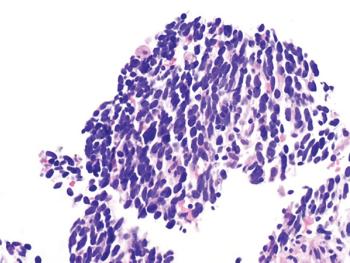

Medical oncologsts discuss the case of a 70-year old woman with synchronous multiple primary lung cancer.